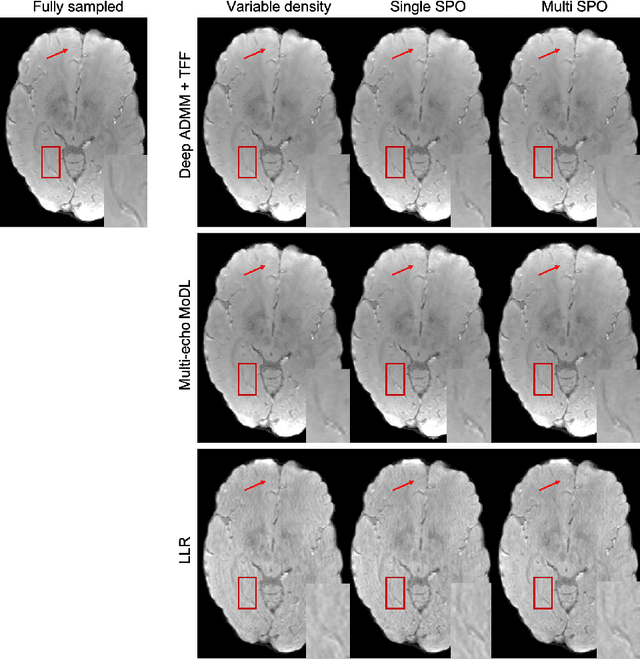

Quantitative imaging in MRI usually involves acquisition and reconstruction of a series of images at multi-echo time points, which possibly requires more scan time and specific reconstruction technique compared to conventional qualitative imaging. In this work, we focus on optimizing the acquisition and reconstruction process of multi-echo gradient echo pulse sequence for quantitative susceptibility mapping as one important quantitative imaging method in MRI. A multi-echo sampling pattern optimization block extended from LOUPE-ST is proposed to optimize the k-space sampling patterns along echoes. Besides, a recurrent temporal feature fusion block is proposed and inserted into a backbone deep ADMM network to capture the signal evolution along echo time during reconstruction. Experiments show that both blocks help improve multi-echo image reconstruction performance.